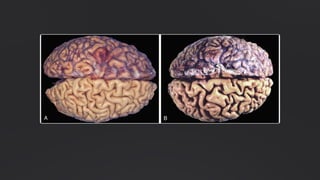

Atrofia

Diminuição do tamanho celular. Causada por redução da carga de

trabalho ou desnutrição.

Exemplo: atrofia uterina após a menopausa.

Atrofia: Redução do Tamanho Celular

Atrofia é a diminuição no tamanho das células por perda de substância celular. Quando um número

suficiente de células está envolvido, todo o tecido ou órgão diminui em tamanho ou torna-se

atrófico . Embora as células atróficas possam apresentar função diminuída, elas não estão mortas.